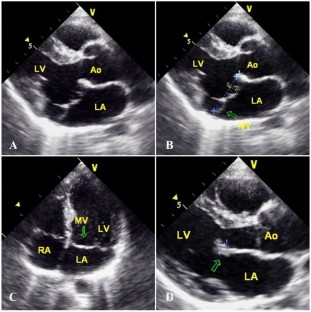

Fig. 1

Fig. 2